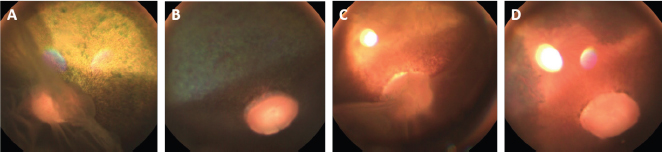

Fig. 2. Case 2 with a permanent globe deviation and scleral show, before (A, B) and after pupil dilatation (C, D). Right eye with lens equator visible at 8 o’clock and vitreous floaters evident after pupil dilatation (C). Left eye with a posterior cortical cataract. The lens equator is visible in the nasal quadrant and the detached retina is evident nasally (D).

The ophthalmic examination of the gelding was identical to that of the mare except for a lateral divergent strabismus with a slight rotation of the globe within the orbit OU regardless of head positioning. The ventronasal sclera were continuously exposed (Fig. 2A and B). The equator of the lens was visible OU after pupil dilation, and an incipient posterior cortical cataract was present OS (Fig. 2C and D). Intraocular pressure measured 27 mmHg OD and 26 mmHg OS.